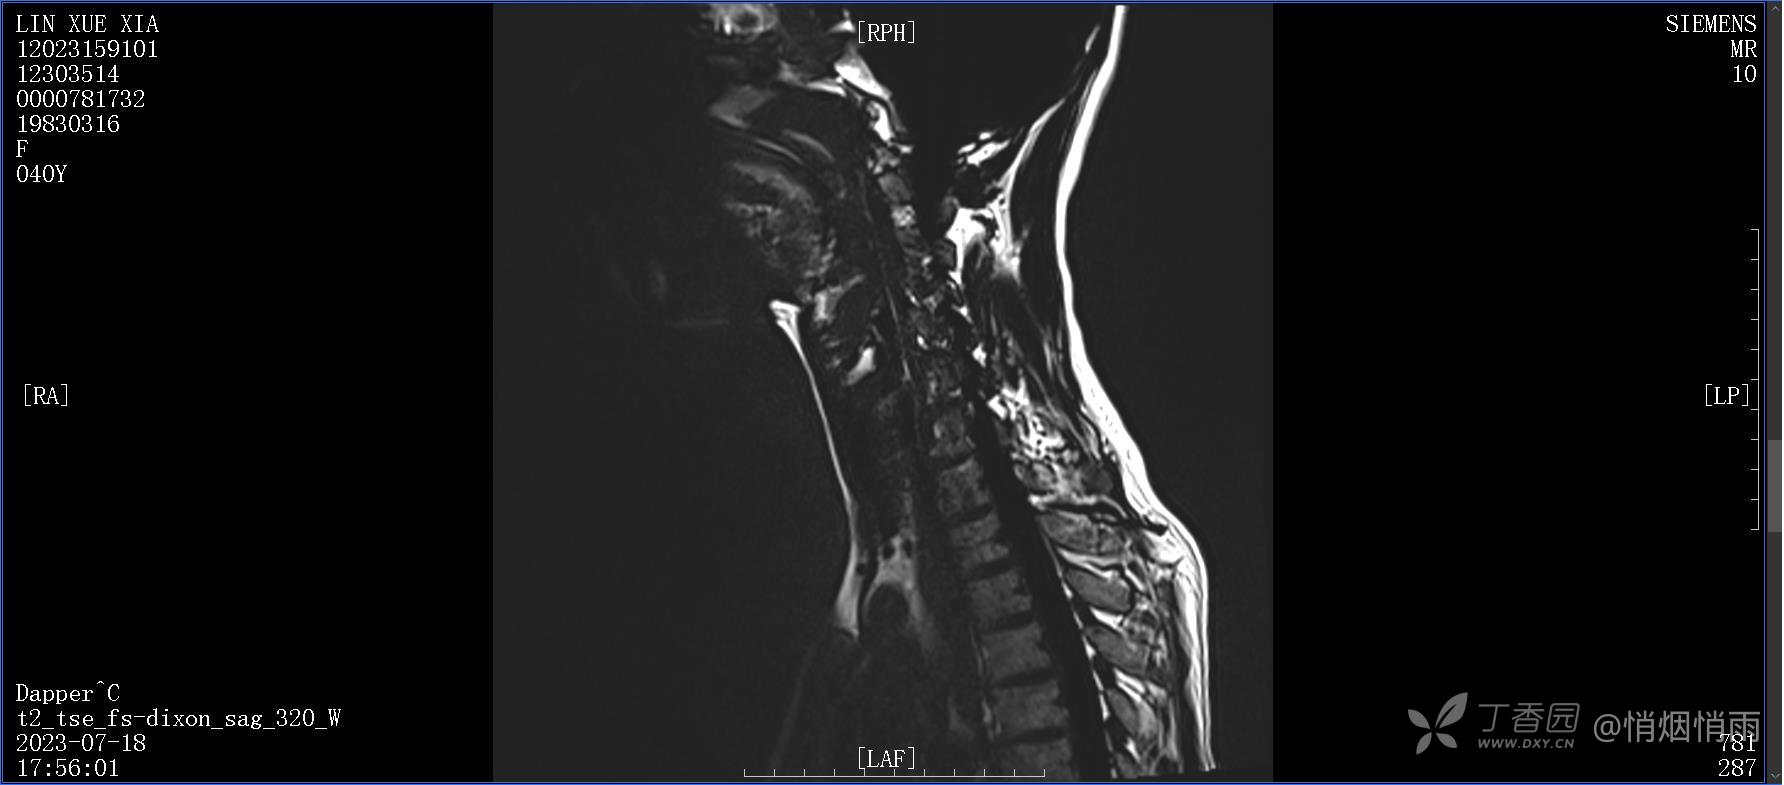

NeurothinkerZ 推荐患者女性,40岁,因右肩背部疼痛班活动受限4日余入院(2023-07-17)。

病史:入院前4天无明显诱因突然感右肩背疼痛伴随活动受限,自行口服依托考昔、艾瑞昔布等药物治疗,院外应用肩关节局部手法按摩等,均无明显改善。外院门诊诊为颈椎病。自诉既往多次“胸椎小关节紊乱”于当地诊所行手法按摩,治疗后好转,否认慢性疾病病史、外伤史、手术史,诉青霉素过敏,无其他药物食物过敏史,否认吸烟史、饮酒史,月经正常,经量正常。

查体:右肩关节局部轻度肿胀,肩胛区压痛明显,痛处不固定,肩关节痛性活动受限,jobe test(+),lift -off test(+),中指、环指感觉较余指减退,余肢端感觉及血运情况可。

目前的诊断,暂时依据辅助检查诊为肩袖损伤,但是患者疼痛的性质和特点,却不是单纯的肩袖损伤所致。考虑过胸廓出口综合征,但是该疾病会出现肩胛区的疼痛吗?(由于考虑到费用的问题,没再进行下一步的检查)带状疱疹会有如此的症状吗?